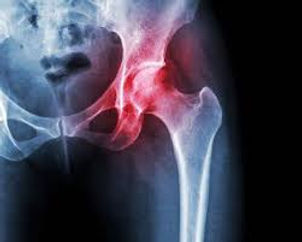

Hip pain can make walking, standing, and even resting uncomfortable. Arthritis, labral irritation, tendon inflammation, and chronic degeneration often worsen over time — and traditional treatments like steroids offer only temporary relief.

✅ Hip Conditions We Treat

Hip arthritis (mild to severe)

Labral irritation

Hip tendonitis (hip flexor, gluteal, adductor)

Bursitis

Degenerative joint disease

Chronic hip pain

Post‑surgical hip pain

Early avascular necrosis (mild cases)